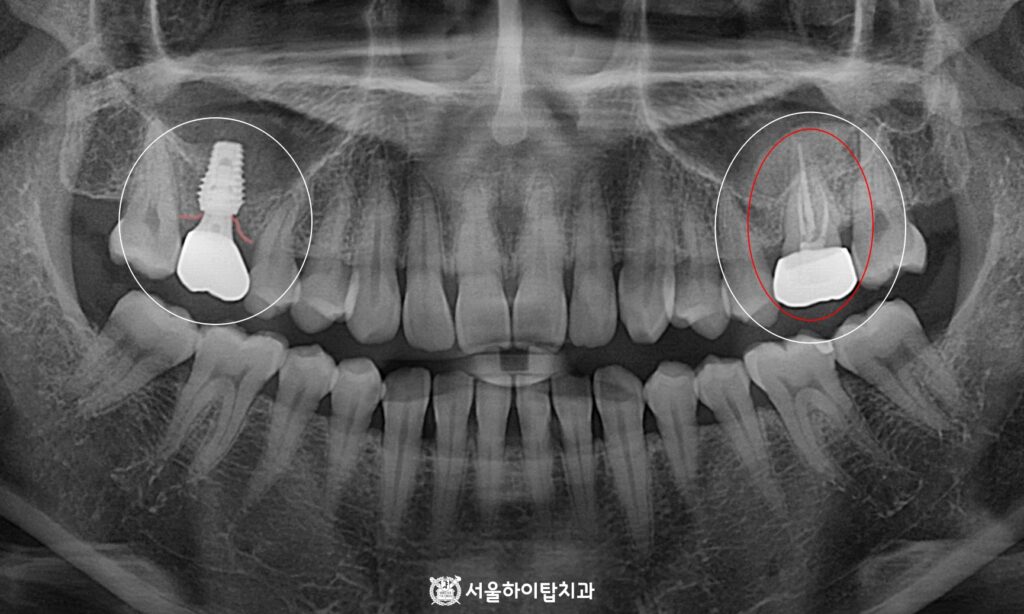

4. 스캔바디 체결

골 유착이 충분히 이루어진 시점에,

최종 보철 연결을 위해 스캔바디를 체결하고

이를 바탕으로 인상채득 과정을 진행합니다.

스캔바디를 통해 임플란트 위치와

잇몸 상태를 정확히 기록할 수 있으며,

이를 기반으로 환자의 교합과 심미성을 고려한

맞춤형 최종 보철을 제작하게 됩니다.

5. 최종 결과

사진 기준 오른쪽 어금니는 신경치료 후

크라운까지 제작 및 장착이 완료되어,

심미성과 기능이 모두 개선되었습니다.

이에 따라 이전에 불편했던 저작 활동도

원활하게 이루어질 것으로 기대됩니다.

왼편 역시 임플란트가 안정적으로 식립되면서,

앞으로는 양쪽 어금니를 균등하게 활용할 수 있어

저작 기능이 더욱 효율적이고 편안하게 개선될 것입니다.

앞으로는 정기검진을 꾸준히 받으시면서,

임플란트와 자연치의 건강 상태를 꼼꼼히 확인하고,

필요한 경우 조기 관리를 진행하는 것이 중요합니다.